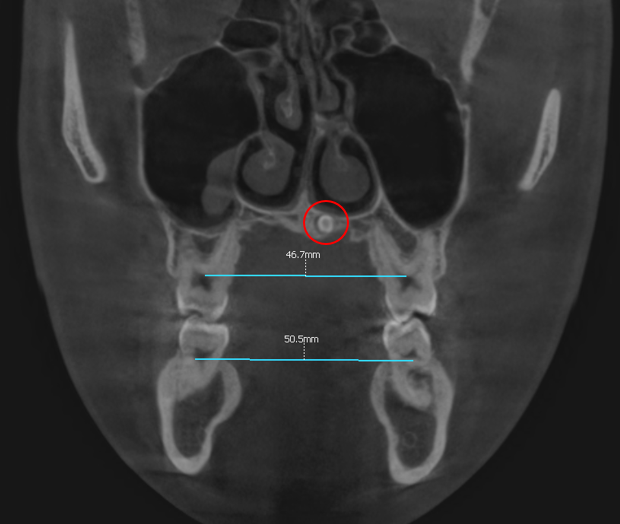

또한 위어금니 간 폭경과 아래 어금니 간 폭경의 비율에서도 부조화가 관찰되었습니다.

정상적으로는 상악이 0-1mm 정도 더 큰 값을 보여야 하는데, 이 비율이 맞지 않아 전체적인 교합의 안정성에 영향을 미치고 있었습니다. → 상악 중절치 사이에 과잉치가 관찰되어 상악골 확장은 하지 않는 방향으로 결정했습니다. 과잉치의 존재는 치료 계획에 중요한 변수가 되며, 이를 고려하지 않은 확장 치료는 오히려 치료 결과에 부정적 영향을 미칠 수 있기 때문입니다.